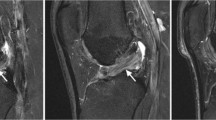

The ROIs were measured at all levels, from the cartilage surface to the deep zones, and the subchondral bone was excluded carefully. Each ROI was measured within a range that measured 55 voxels high and 40 voxels wide [5,8] (Figure 1). We evaluated and recorded the Outerbridge grade of the damaged areas of cartilage during surgery, confirmed arthroscopic photographs during measurement of cartilage damage using MRI, and had another doctor reevaluate the Outerbridge grade. Three orthopaedic surgeons and one radiologist, having board certificate of The Japanese Orthopaedic Association and Japan Radiological Society, separately measured the areas of cartilage damage on the MRI. To minimize disparities, the measurements were obtained three times and the mean value calculated.

A 21-year-old man sprained his knee while kickboxing. Five months later, he landed awkwardly in a hurdle touchdown and sprained his knee again. Giving way persisted and investigations revealed a right anterior cruciate ligament (ACL) injury and right medial meniscus injury. The patient was treated with ligament reconstruction and meniscal suture (Figure 4).

DT imaging in the early cartilage damage. The patient underwent surgery for right knee ACL and medial meniscus injury. In the inner femoral condyle, a cartilage crack caused by the medial meniscus rupture was observed to have Outerbridge grade 1 damage. The ADC for this area was measured as 1.75 × 10−3 mm2/s.

A 61-year-old man who had previously undergone meniscectomy in the right knee. He had pain on the inside of the right knee while walking and was being given oral analgesics treatment and injections by his local physician. However, the patient showed no improvement and was referred to our department for further examination. The patient was subsequently diagnosed with osteoarthritis of the right knee and underwent high tibial osteotomy (Figure 5).

DT imaging in the severe cartilage damage. The patient underwent surgery for a right knee medial meniscus injury. Outerbridge grade 3 cartilage damage caused by the medial meniscus rupture was observed throughout the entire inner femoral condyle. The ADC for this area was measured as 2.15 × 10−3 mm2/s.